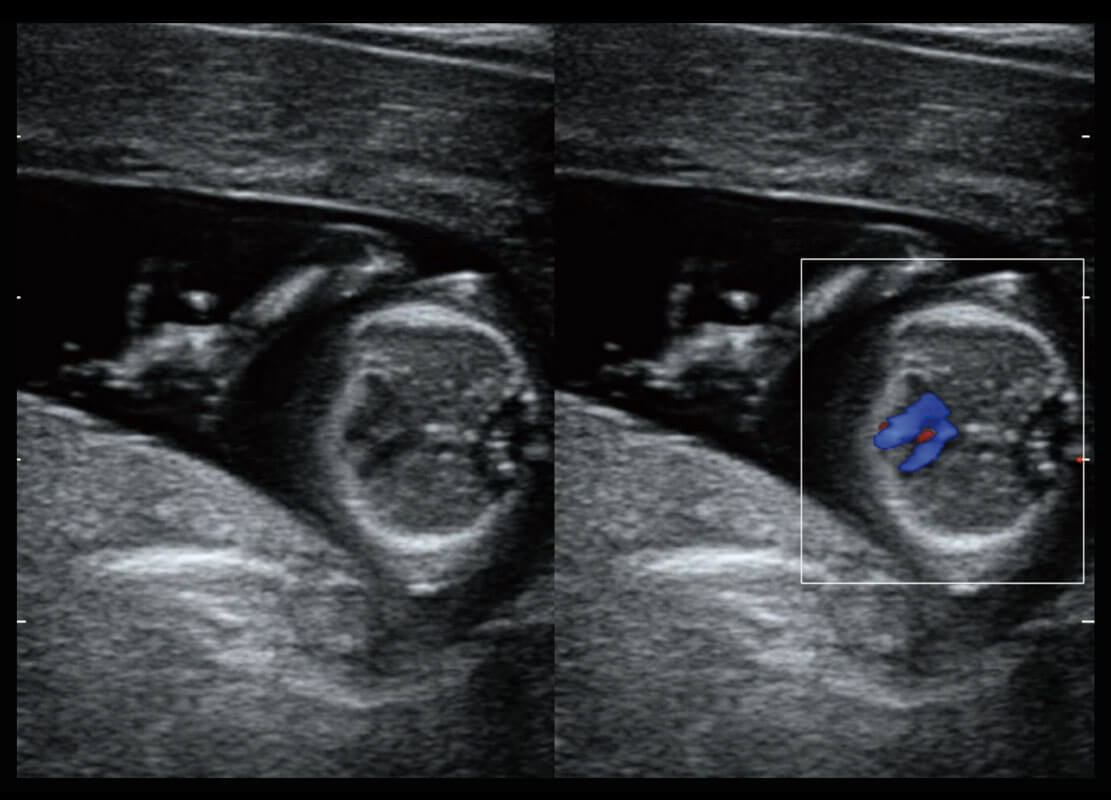

乳腺超声 / 新生儿

P60搭载宽频带线阵探头、宽景成像、弹性成像技术,为您提供乳腺应用方案。P60支持高频相控阵探头、线阵探头、腹部高频探头、腹部微凸探头等,丰富的探头群搭载敏感的彩色血流成像,适用于新生儿多种脏器检测要求,满足新生儿筛查需求。

• 新生儿心脏